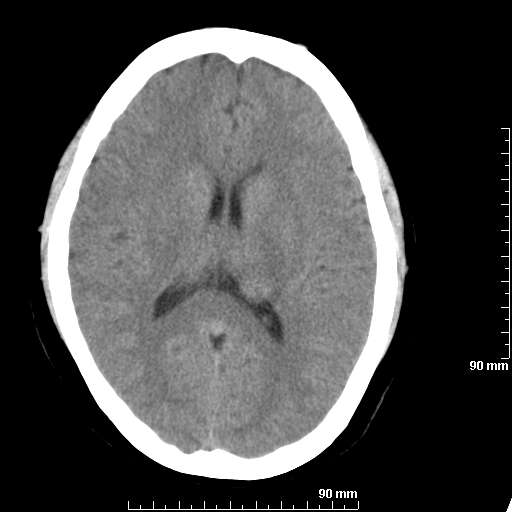

[维修案例解析] 大家猜猜看,这个伪影是怎样产生的.

二马日王 显示全部楼层 发表于 2011-6-9 18:12:55 |阅读模式

我院西门子单排CT由于一零件受损而产生的伪影.

哈哈,都不是。是虑线器fiter裂损。大家没想到吧。

哦,跟脑出血有点像哦

形状不规则,边缘模糊。比较特殊的一种伪影哈!

这种伪影很常见!伪影应该是在视野的中心的。

西门子的虑线器fiter裂损这才是很难见的问题,GE的最常见

虑线器老化,中间崩裂一块掉了